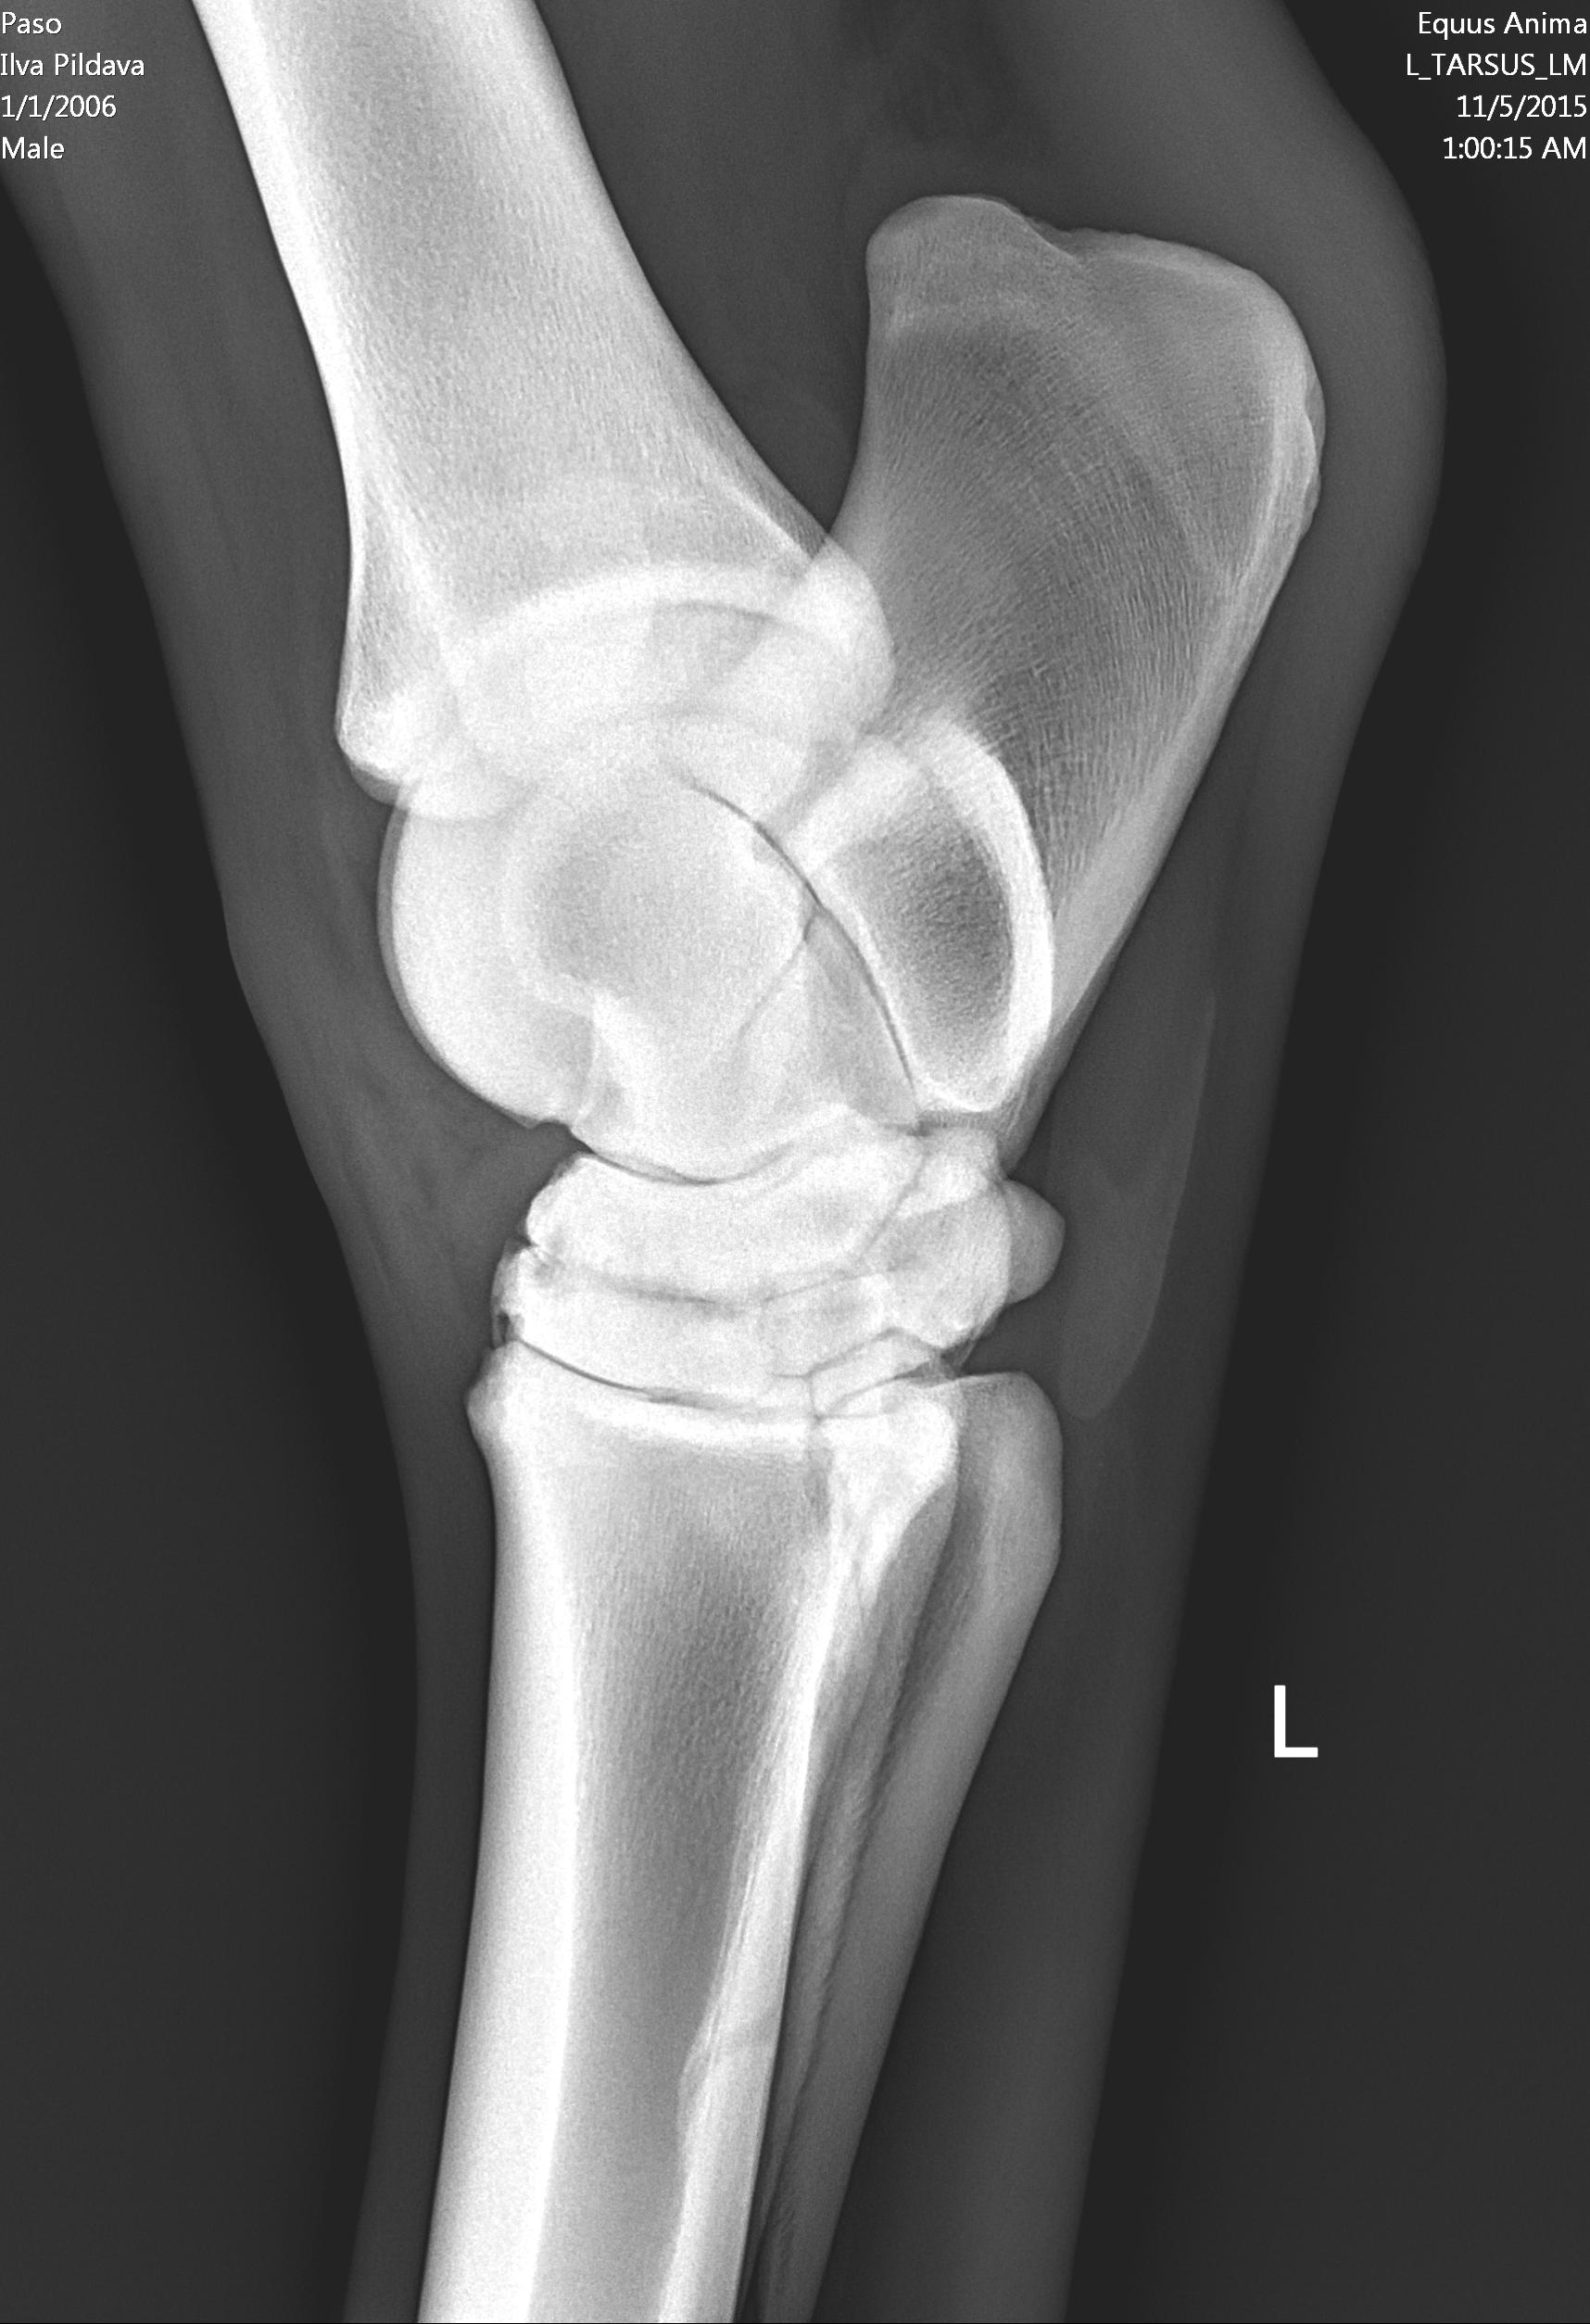

U majei loshadi ( 10 let) kastrat, v proslom godu obnaruzili spat I sdelali kurss Tildren, 16.10.2017. ehso odin kurss, daju polgoda eto http://ru.eggersmann.info/432_/132_Profi_Gelenk_aktiv.html, I vot kakije u loshadi rentgeni po datam. Prigaju do 110 cm, edu na sorevnavanije, idjot on horosho. esli stojal v bokse , snachala hromaet,no potom 2-4 minuti v risi i prohodit. Ja bi hotela prigatj vishe,no bojus ,mozno li. Letom dva raza bila ,chto v trenirovke zahramal ochen silno,no cerez paru chasov ,vsjo proslo.

Vopros,kakije prognozi, chto esje davatj I kakje nagruzki mozno? U nas malo opita s Tildren,potomu kazdij govorit svojo.